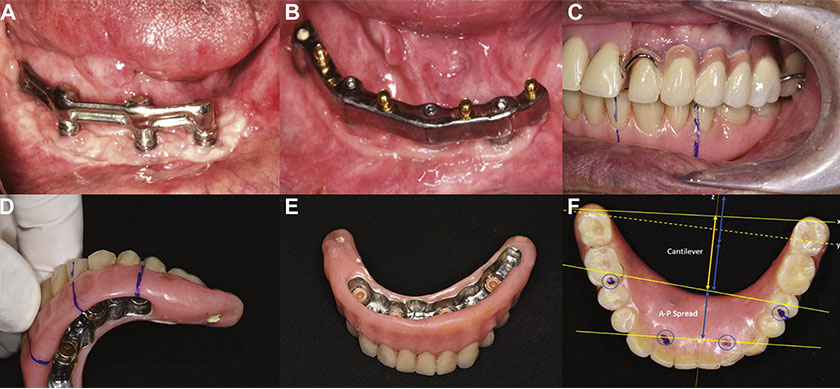

An overdenture supported on a bar-retained, implant-supported system was delivered 6 months later (Fig 3). The prosthesis was designed with distal cantilevers, especially on the left side where the fixed prosthesis was opposed. The position of the posterior abutments on the denture was located between the premolar and molar on the right and on the mesial of the second premolar on the left (Fig 3). The left cantilever extended to 2 teeth composing the 2 molars, and the right cantilever extended to 1 tooth. On the left, the denture was adjusted so that only the mesial part of the left second molar occluded to the opposing tooth. The patient was scheduled for continuous follow-up assessments. After 3 years, the bar-retained supporting system appeared loose and was replaced with the new CAD/CAM milled bar with the OT Equator system on the same 4 implants (Fig 3). The total follow-up time was 82 months (Fig 4).

Figure 3. The secondary phase of implant placement 6 months later. A, The bar-retained supporting system and the prosthesis. B, After 3 years, the system was replaced with a new CAD/CAM milled bar-retained supporting system with the OT Equator system on the same 4 implants. C, D, E, The prosthesis with the cantilevers. F, The relation of the cantilever length (yellow arrow) and the anterior-posterior (A-P) spread (blue arrow).

The 4 installed implants presented good initial stability (35 N/cm) and good osseointegration based on an orthopantomographic image (Fig 3). Bone remodeling was observed around the implant shoulder. The zone of keratinized soft tissue around the dental implants and supporting overdenture was expanded.